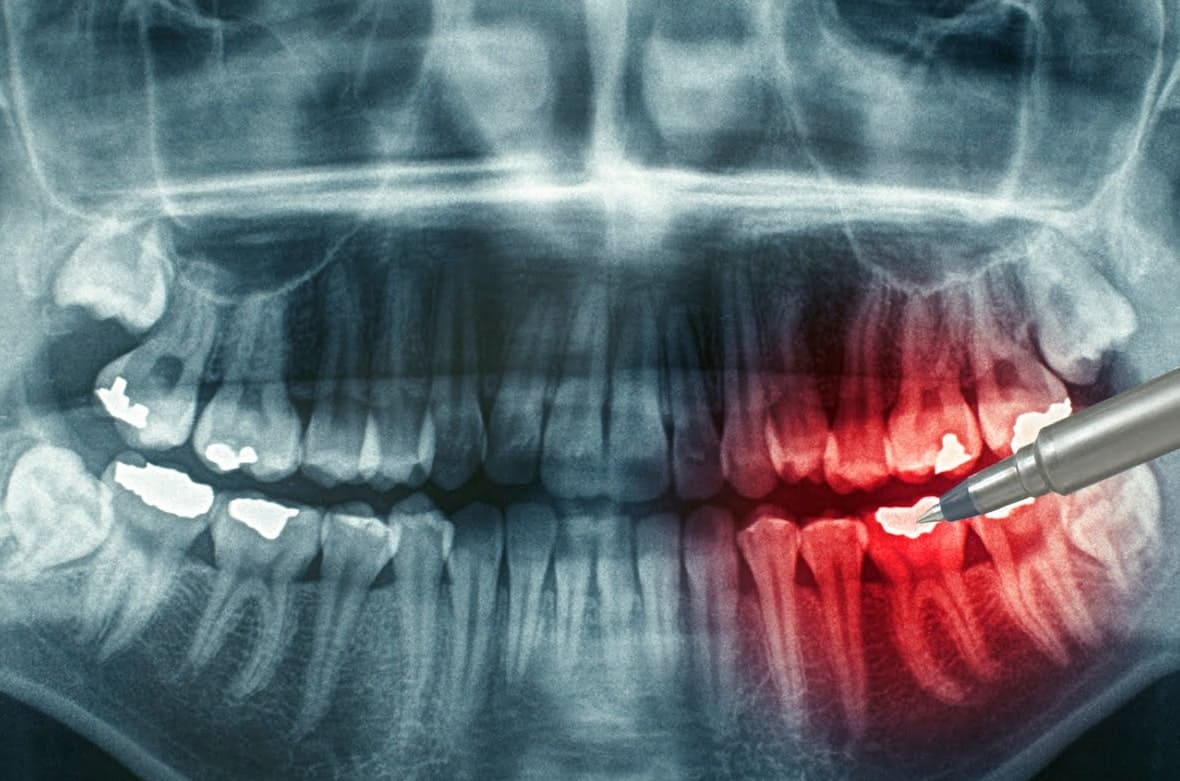

Здесь также целесообразно отметить, что на начальных этапах симптомы могут казаться незначительными — и это усложняет диагностику. Поэтому если речь идет об одонтогенном сепсисе, очень важно обращаться к опытным врачам и в клинику с современным, точным оборудованием. Это поможет вовремя выявить проблему даже на ранних стадиях и провести необходимое лечение.

Специалисты помогут вам точно определить источник инфекции в полости рта и оценить, насколько поражены ткани. После диагностики стоматологи подберут лечение и будут контролировать течение терапии.